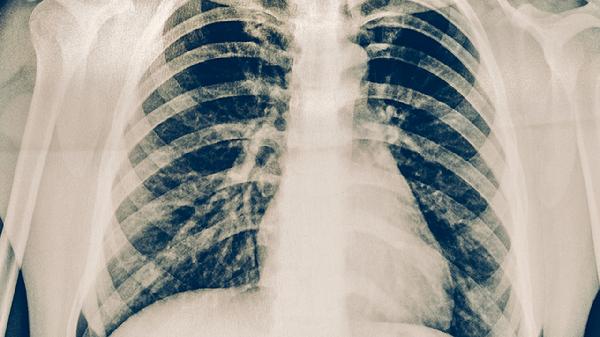

肺結(jié)核病患者的飲食烹飪方法是什么

肺結(jié)核病患者的飲食烹飪方法主要有蒸煮、燉湯、清炒、涼拌、熬粥等。肺結(jié)核患者需保證優(yōu)質(zhì)蛋白和維生素攝入,烹飪時(shí)需兼顧營(yíng)養(yǎng)與消化吸收。